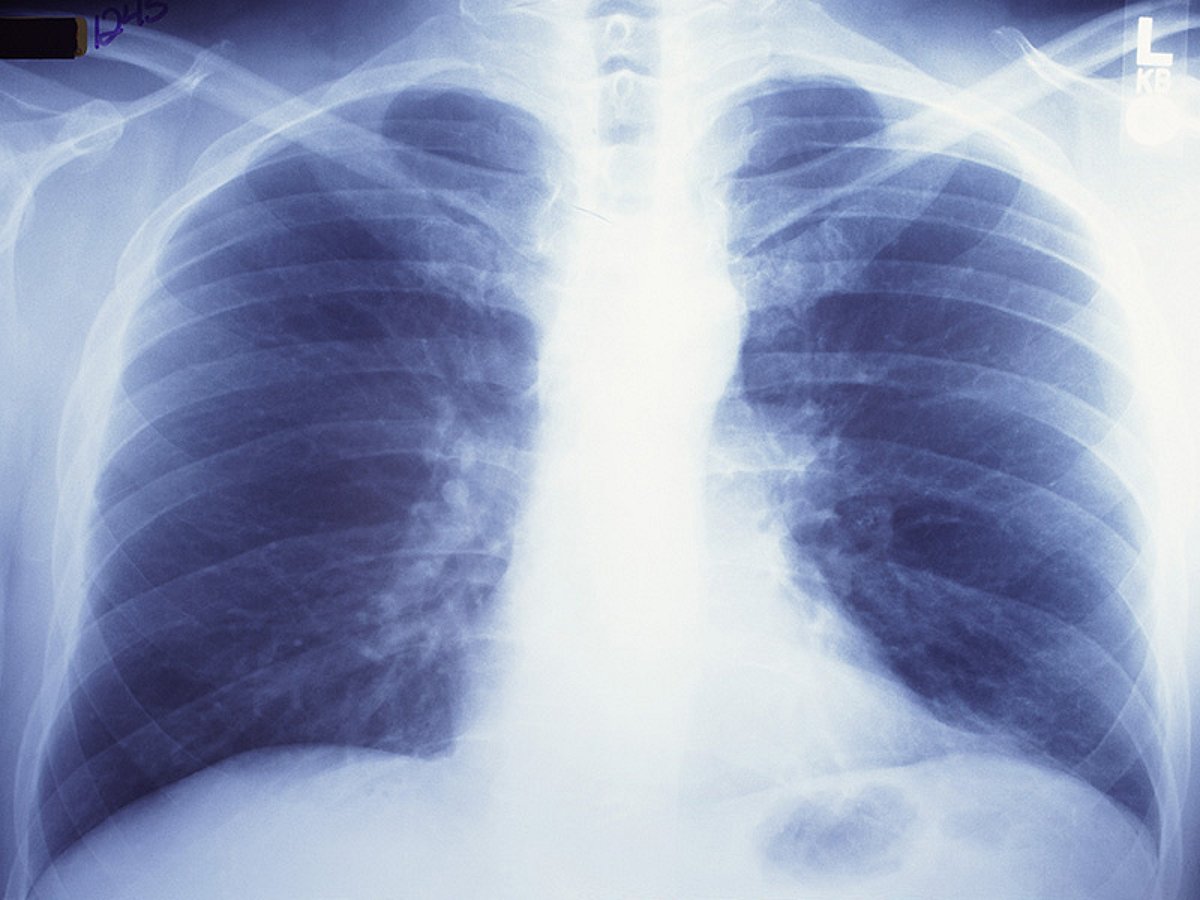

Рентген здоровых легких: примеры снимков и советы

Раздел: Сокровищница опыта